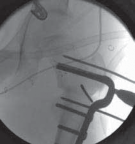

1. In older ambulatory children with healthy bone, the seating chisel should be intermittently backed out to prevent its impaction in the strong bone.

2. It is prudent to back the chisel out, short of its final resting position, before completion of the osteotomy to facilitate its removal in exchange for the blade plate (

TECH FIG 2E

).

--- TECH FIG 2 • Intraoperative C-arm–guided insertion of the seating chisel for the blade plate.A. Insertion of the guide pin in the superior part of the neck at right angles to the long axis of the femur. B. Position of the guide pin along the midfemoral neck axis in the frog-leg lateral view. C. Position of the seating chisel parallel to the guide pin and perpendicular to the long axis of the femur. D. Position of the seating chisel parallel to the guide pin and along the midfemoral neck axis on the frog-leg lateral view. E. The seating chisel is backed out from its final position to disimpact the chisel before the osteotomy.Pr FiAE